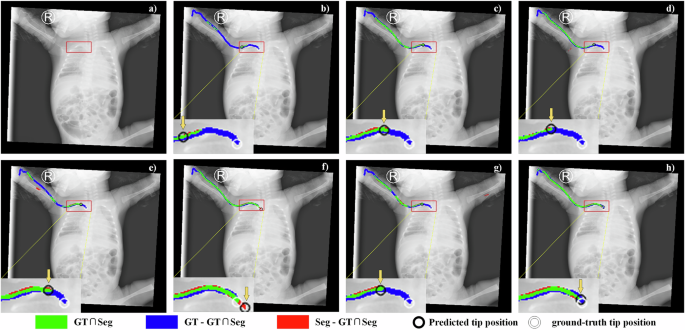

Tip localization: Although the proposed method achieves continuous and complete PICC line segmentation (see Figs. 2 and 3, and Tables 1–3), clinical practice prioritizes accurate tip localization over full-line segmentation due to the risk of severe complications from malpositioned tips. In this work, PICC tip position is defined by tracing the terminal endpoint of skeletonized segmented result. Figure 4 shows a representative pediatric PICC radiograph with segmented results and tip detections across different methods. White rings indicate ground-truth tip positions, while black rings mark predicted tip positions. While all methods generate tip predictions, their accuracy varies significantly. For instance, the predicted tip position in (b) lies farther from ground truth than other methods. (e) and (f) achieve closer proximity to ground truth than (c), (d), and (g), while (h) presents near-perfect alignment between predicted and actual tip positions. The comparative results validate the superior tip localization accuracy of proposed method.

Red squares denote the zone of the PICC tip. a Representative pediatric PICC radiograph from Center I. b–h Segmentation and tip localization results from comparative methods. White rings denote ground-truth tip positions, and black rings indicate predicted tip positions. Yellow arrows highlight the position of the black rings.

Center II: To evaluate the model’s robustness and generalizability, external validation is conducted using an dataset from Center II. Figure 5 illustrates the segmentation results of a representative pediatric PICC radiograph from this center. Figure 5a–g displays the segmentation and tip localization results produced by DFANet, FSNet, MDANet, MISSFormer, RSF-Conv, UNet++, and TopNet, respectively, while (h) provides the manual ground-truth annotation. In terms of segmentation completeness, several models (a–d) exhibit significant under-segmentation, whereas others (e, f) achieve better coverage at the risk of introducing false positives. Regarding continuity, gaps or discontinuities are commonly observed in outputs (a–f). In contrast, TopNet (g) effectively addresses both completeness and continuity issues. For tip localization accuracy, models such as UNet++ (f) show substantial placement errors, while RSF-Conv (e) and TopNet (g) demonstrate superior performance, with only minimal deviation from the actual tip location. This comparative visualization underscores the distinct strengths and limitations of each method. Accurate tip localization is critical, and models exhibiting high TDE or fragmented segmentations are considered clinically unreliable due to the potential for misinterpretation. TopNet exhibits promising performance, closely approximating the expert-annotated ground truth.

Center III: To further assess the TopNet’s robustness and generalizability, another external validation is performed using data from Center III. Figure 6 depicts the segmentation results of a representative pediatric PICC radiograph obtained from this center. The manual annotation in (h) provides the ground-truth reference for evaluating the automated results presented in (a–g). Notable variations in performance are observed across the automated methods in terms of both segmentation accuracy and tip localization. TopNet (g) clearly demonstrates superior performance, with segmentation contours that align most closely with the ground truth in both morphology and continuity. Its tip localization is precise and reliable, showing only minimal divergence from the reference (h), which indicates strong feature extraction capabilities and generalizability. UNet++ also delivers competitive results, although some minor discrepancies are observable. In contrast, the remaining methods, particularly DFANet and FSNet, exhibit substantial limitations in segmentation quality and tip positioning, underscoring their constrained clinical applicability for reliable PICC assessment.